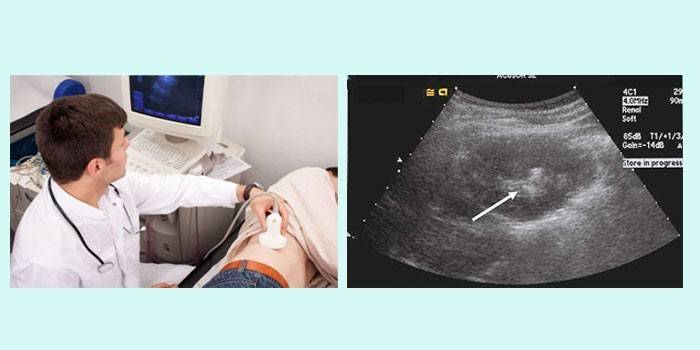

- Ultrasonido: evalúa los cambios en la estructura del cuerpo, determina la presencia y la ubicación de los cálculos.